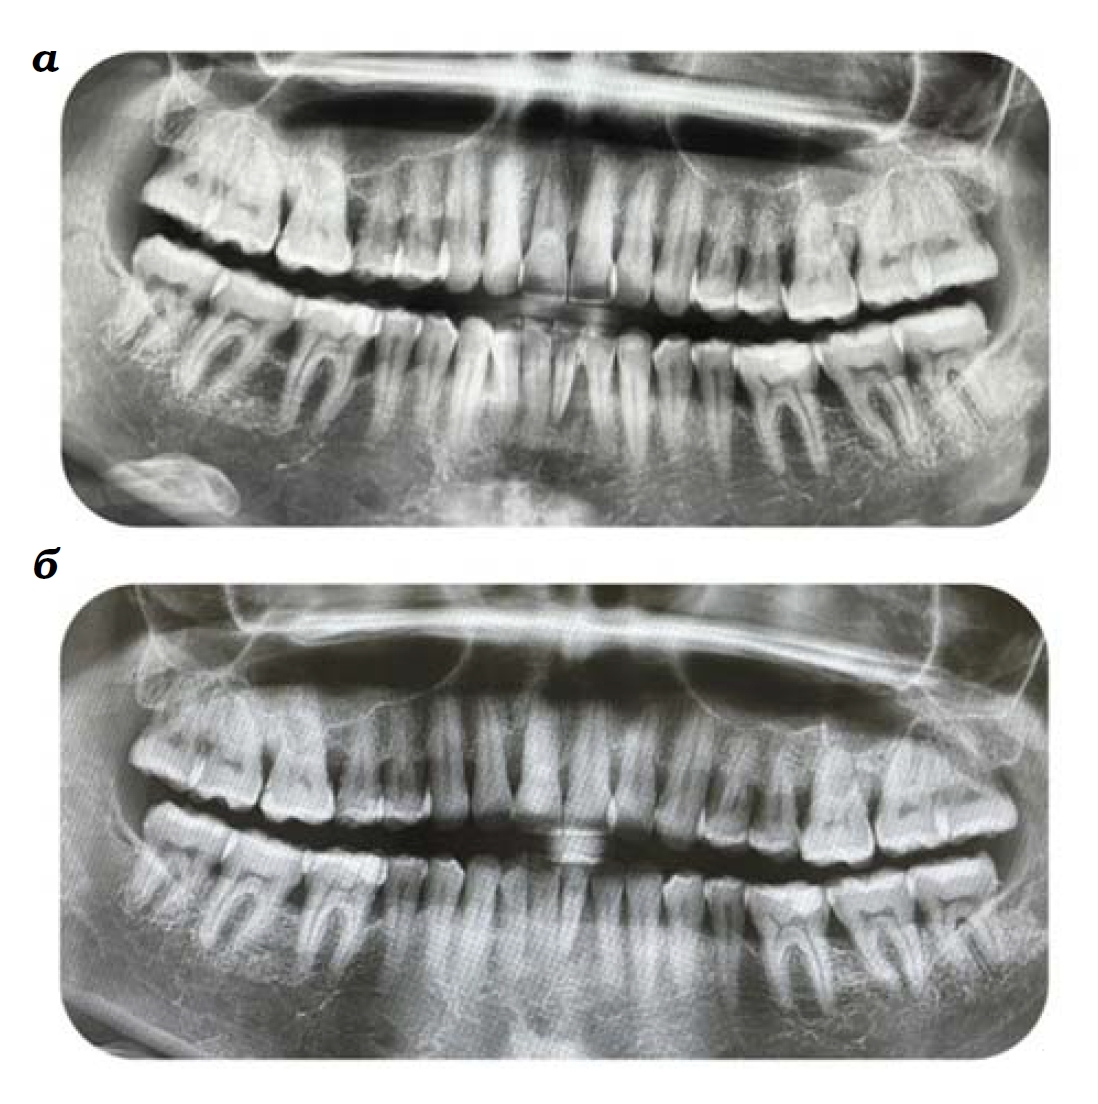

Медицинские Исследования: Кортикальная Пластинка на ОПТГ